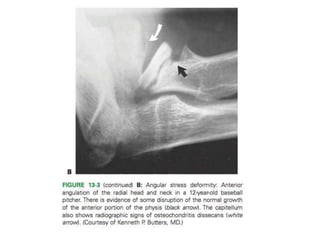

Group III: Stress Injuries

Angular injuries

Stress Injuries (Group III)

Increasing grade has generally been associated with poorer outcomes with both nonoperative and ope